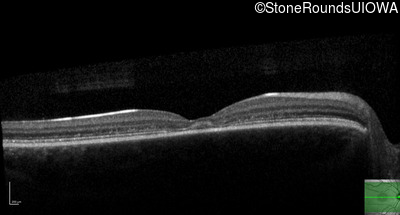

AR Stargardt Disease (IIA)

Age at visit:

14 years

OD

OS

20/32

20/20 -2

OCT Stack

AR Stargardt Disease

ABCA4

Gly607Arg GGG>AGG

Gly1961Glu GGA>GAA

AR